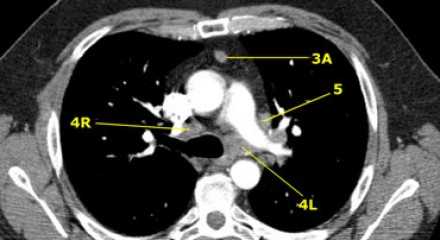

На левом изображении над уровнем легочного ствола представлены нижние паратрахеальные узлы слева и справа, так же здесь представлены узлы 3 и 5 групп.

Изображение слева выше уровня карины. Слева от трахеи 4L узлы. Обратите внимание что они расположены между легочным стволом и аортой, но не в аортопульмональном окне, потому что они лежат медиальнее артериальной связки. Лимфатические узлы латеральнее легочного ствола относятся к 5 группе.